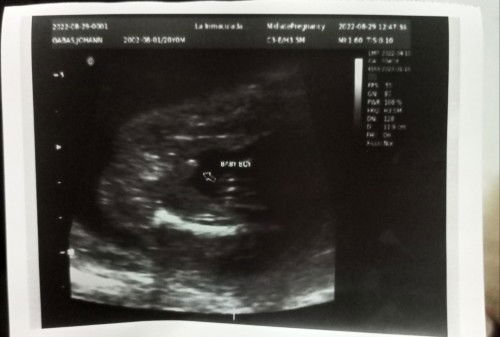

baby boy??

may lawit po . lalaki po sure😊